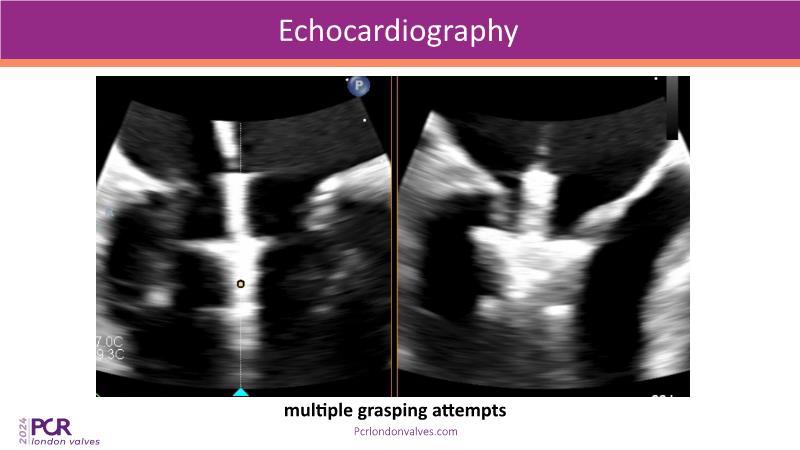

This session examines two compelling cases: a 78-year-old woman with paroxysmal atrial fibrillation, chest trauma, an osteoporotic sternum fracture, and NYHA II exertional dyspnoea, and an 82-year-old man with chronic three-vessel coronary artery disease, bradycardic AF, peripheral arterial disease, spinal stenosis, and chronic kidney disease. Through their study, discover the intricate anatomy of atrioventricular valves, the therapeutic challenges they pose, and the growing significance of transcatheter edge-to-edge repair (TEER) therapies. The discussion also highlights the value of multidisciplinary strategies in managing complex valve diseases effectively.